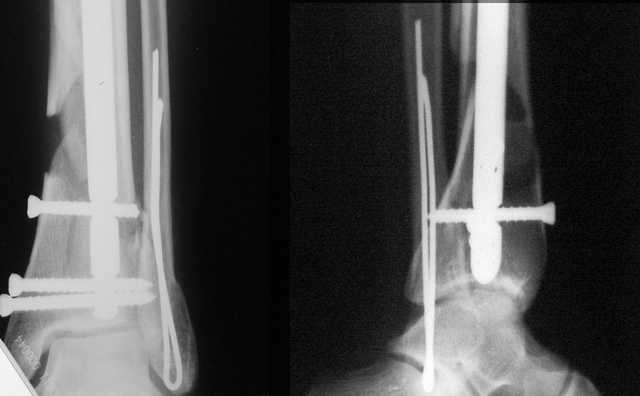

АЧ>Какие тут аргументы в пользу выбора пластины, а не интрамедуллярного гвоздя?

Классически показанием для locked nail яв-ся зоны BC CD, до появления LCP показания к locked nail несколько расширялись в зоны AB и DE

Аргументы: перелом достаточно низкий, трудно будет ввести 3-и блок. винта, а учитывая характер перелома на 2-х дистальных винтах я бы не рекомендовал немедленную полную нагрузку.

АМ> Аргументы: перелом достаточно низкий, трудно будет ввести 3-и блок.

АМ> винта, а учитывая характер перелома на 2-х дистальных винтах я бы не

АМ> рекомендовал немедленную полную нагрузку.

Положим, и с 2 винтами она к 2 месяцам была бы тут вполне реальна. Кроме того, есть возможность ввести винты мимо гвоздя (Poller), и таки разрешить раннюю полную нагрузку (что еще зависит от массы тела пациента и диаметра винтов). А уж если сопоставить стоимость отечественного гвоздика и пластины Synthes... Если бы на порядок более дорогая железка давала на тот же порядок лучший результат... ;-)